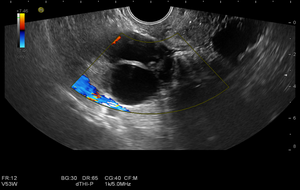

Мультипараметрическое ультразвуковое исследование органов малого таза у женщин (ТВУЗИ-трансвагинальное ультразвуковое исследование)

- Исследование в режиме ЦДК и ЭДК